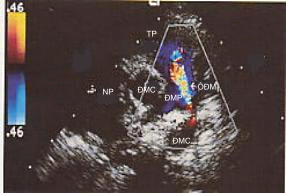

1. Hình ảnh trực tiếp của ống động mạch trên siêu âm 2D thấy đợc ở mặt cắt trên ức và qua các gốc động mạch lớn. Đo đường kính và đánh giá hình thái của ống. Siêu âm Doppler mầu xác định chính xác vị trí đổ vào ĐMP của ống động mạch.

Đánh giá chênh áp qua ống động mạch bằng siêu âm Doppler, từ đó xác định một cách gián tiếp áp lực động mạch phổi (cần đo huyết áp động mạch khi làm siêu âm tim). Quan sát quai ĐMC để tìm các tổn thương phối hợp.

Hình 29-2. Dòng chảy qua ống động mạch trên siêu âm Doppler mầu.

3. Đánh giá mức độ của dòng shunt: dòng shunt tráiđ phải lớn khi thấy giãn buồng nhĩ trái, thất trái và thân ĐMP. Cần đánh giá áp lực ĐMP đã tăng cố định cha, độ dầy của thành thất phải, dòng chảy qua ống động mạch yếu hoặc hai chiều, áp lực ĐMP tăng nhiều gần bằng hay đã vợt áp lực đại tuần hoàn.